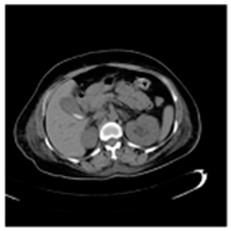

| Original Medical Images | |||||||

| Pair 1 | Pair 2 | Pair 3 | Pair 4 | ||||

![]() (1-9) PSNR = 44.14 | ![]() (1-10) PSNR = 41.90 | ![]() (1-11) PSNR = 40.09 | ![]() (1-12) PSNR = 41.41 | ![]() (1-13) PSNR = 42.24 | ![]() (1-14) PSNR = 40.35 | ![]() (1-15) PSNR = 40.79 | ![]() (1-16) PSNR = 40.84 |

| Shadow Images Produced by Using LSBs | |||||||

![]() (1-17) PSNR = 26.35 | ![]() (1-18) PSNR = 25.49 | ![]() (1-19) PSNR = 23.57 | ![]() (1-20) PSNR = 24.19 | ![]() (1-21) PSNR = 24.79 | ![]() (1-22) PSNR = 24.23 | ![]() (1-23) PSNR = 23.26 | ![]() (1-24) PSNR = 24.42 |

| Shadow Images Produced by Using Middle Bits | |||||||

![]() (1-25) PSNR = 18.97 | ![]() (1-26) PSNR = 19.95 | ![]() (1-27) PSNR = 14.10 | ![]() (1-28) PSNR = 13.84 | ![]() (1-29) PSNR = 16.66 | ![]() (1-30) PSNR = 13.23 | ![]() (1-31) PSNR = 13.38 | ![]() (1-32) PSNR = 14.75 |

| Shadow Images Produced by Using MSBs | |||||||